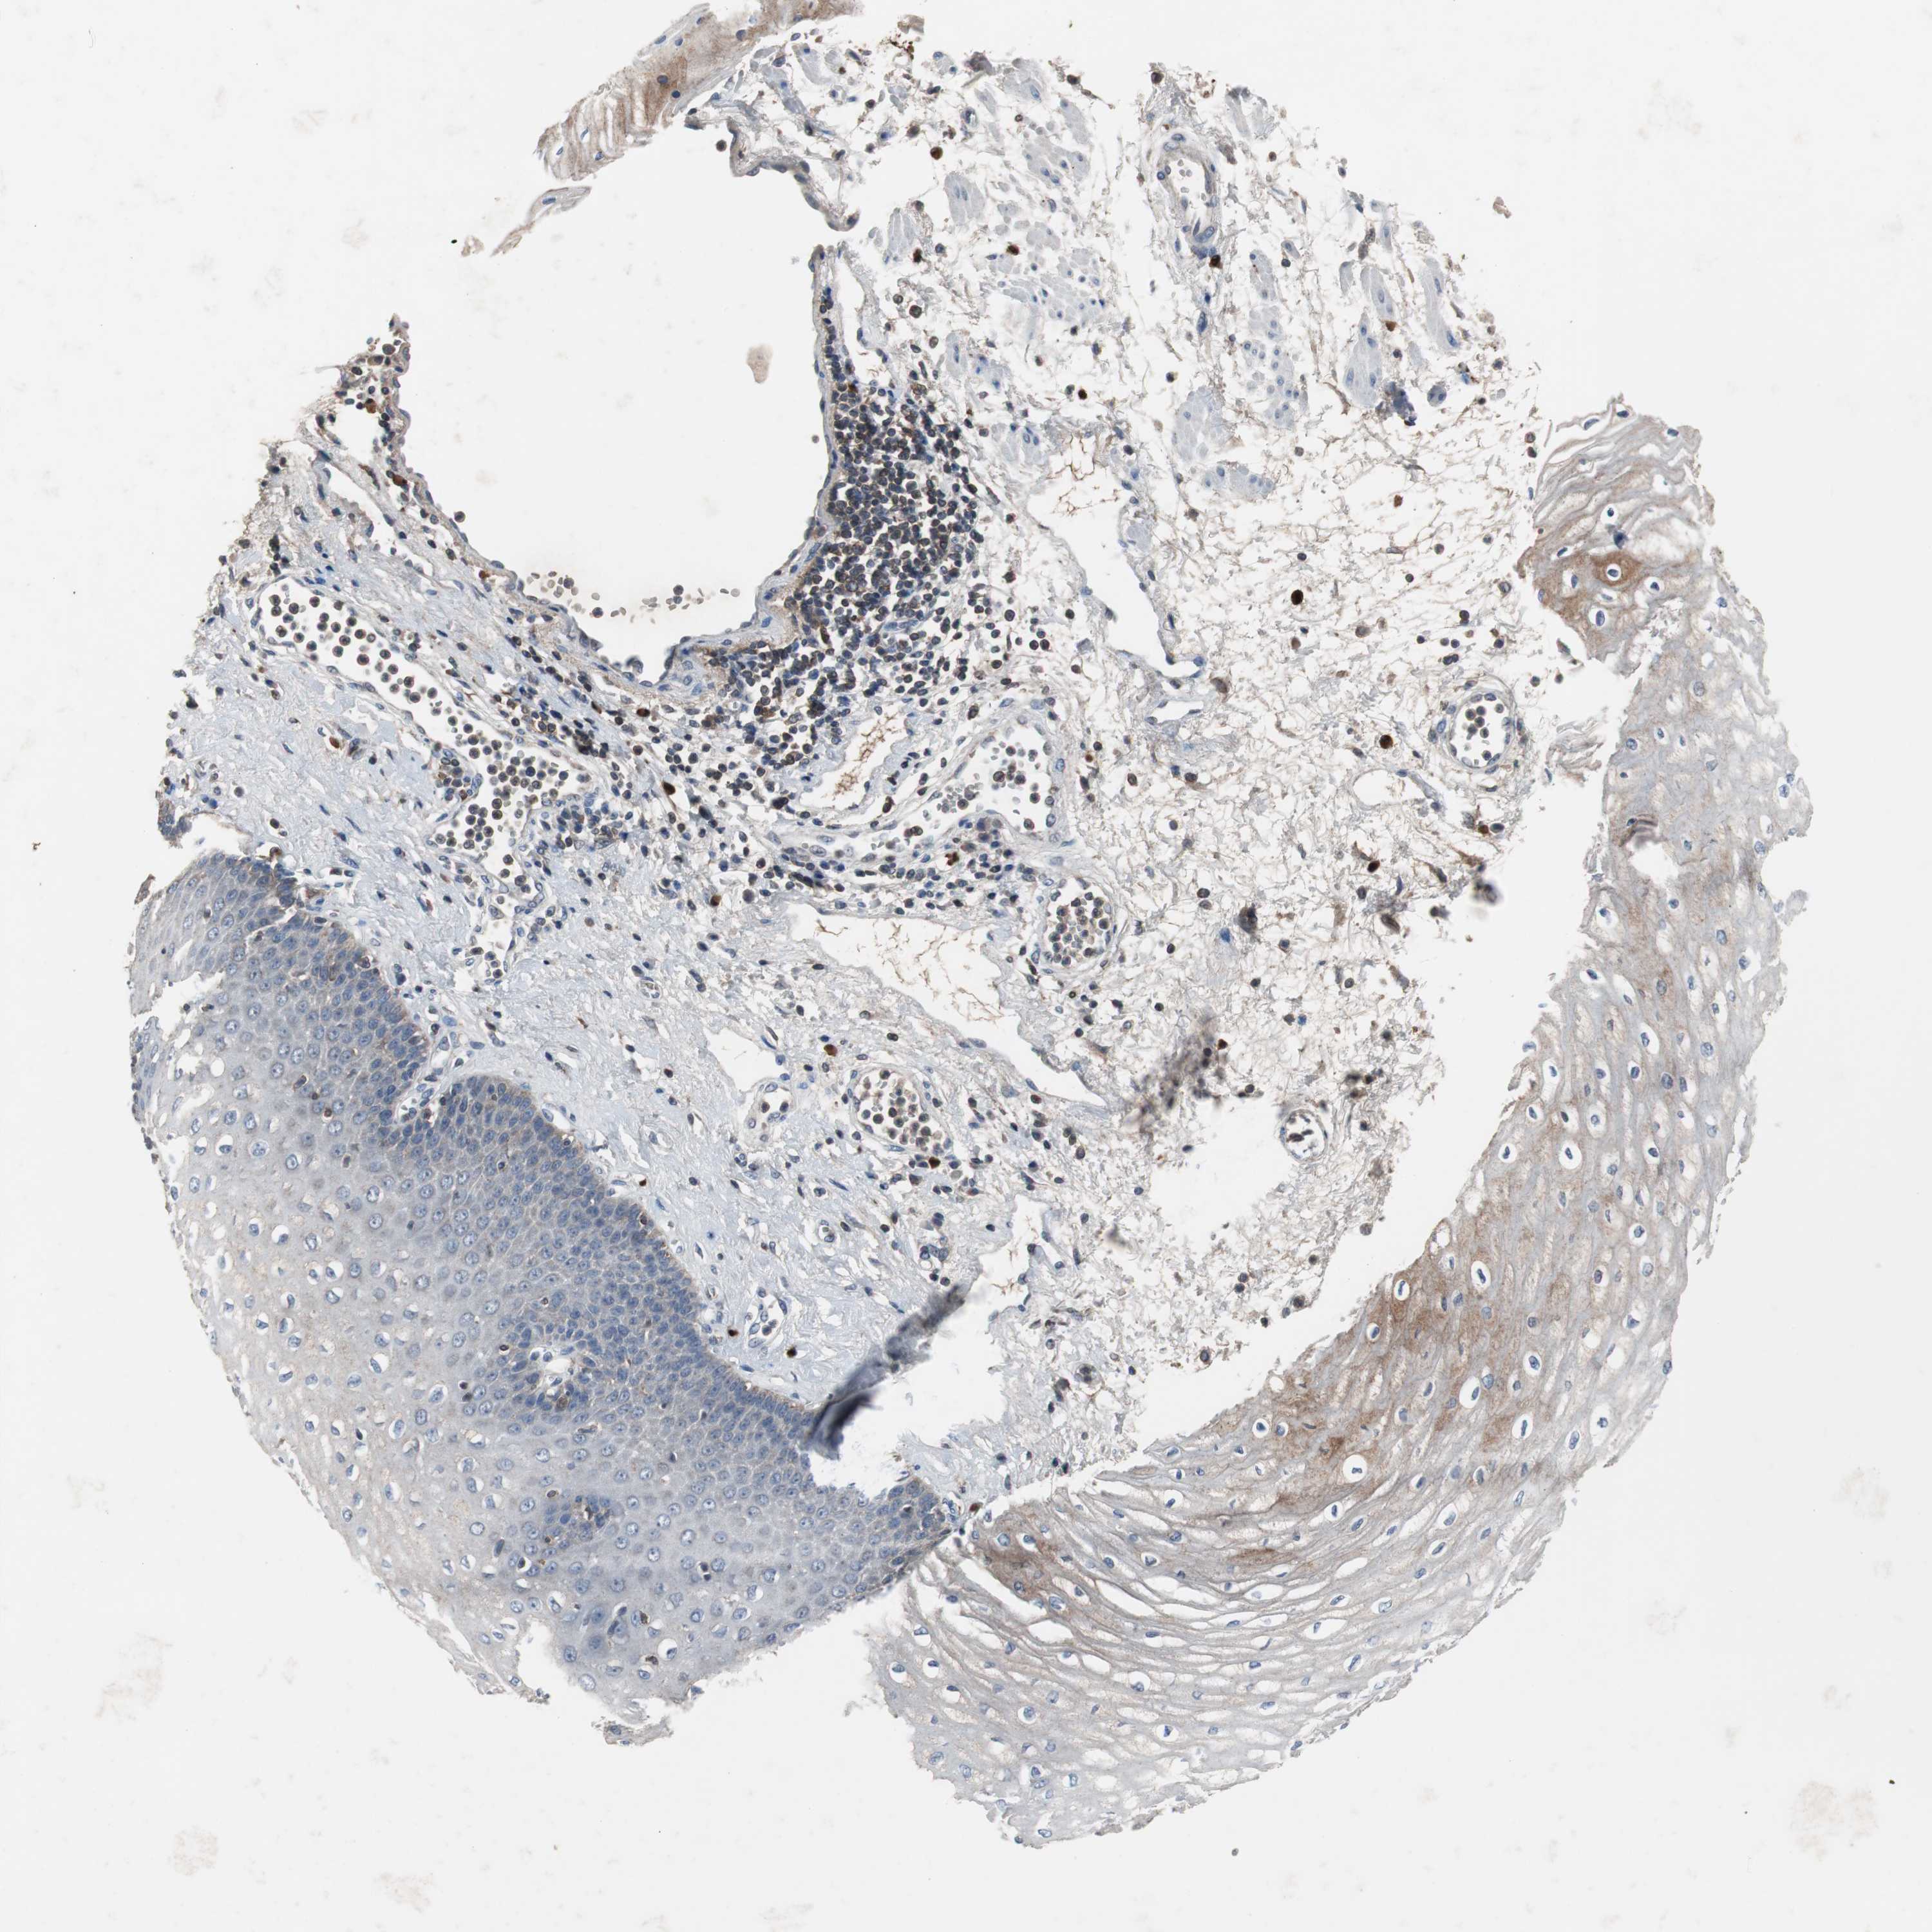

ESOPHAGUS - Antibody stainingi

Antibody staining in the annotated cell types in the current human tissue is reported as not detected, low, medium, or high, based on conventional immunohistochemistry profiling in selected tissues. This score is based on the combination of the staining intensity and fraction of stained cells.

Each image is clickable and will lead to virtual microscopy that enables deeper exploration of all samples and also displays staining intensity scores, fraction scores and subcellular localization as well as patient and tissue information for each sample.

Antibody HPA007305Antibody HPA007306Antibody CAB000106

Squamous epithelial cells Not detectedLowNot detected